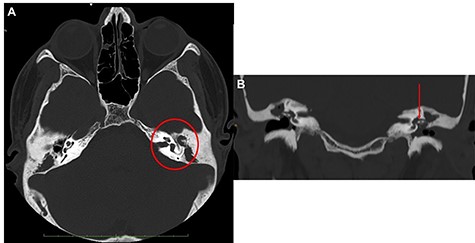

The otoscopic examination revealed bilateral perforation of the tympanic membrane and the presence of purulent discharge in the left ear (Fig. 1B). Nasal endoscopy identified II grade adenoid hypertrophy with complete obliteration of left choanal opening and tubal ostium (Fig. 2A and B). A pure tone audiometry, performed only through bone conduction, showed bilaterally normal auditory threshold. Neck ultrasound identified the presence of abundant fluid in the left latero-cervical area, which extended from the retro-auricular region up to the ipsilateral supraclavicular area.

(A) axial view; the red arrow shows edematous torus tubarius; compared to contralateral, the adenoid is hypertrophic but median; the presence of both these conditions contributes to ostium obstruction of the left tuba (B); (C–E) from top to down, the red asterisk shows the imbibition of sternocleidomastoid muscle sign of BA.

Head and neck contrast-enhanced computed tomography (CT) scan confirmed the presence of the fluid below the left sternocleidomastoid muscle (Fig. 2C–E) with massive opacification of the mastoid cells and the middle ear (Fig. 3A). Inflammatory tissue was identified in the middle ear with erosion of the ossicular bone chain (Fig. 3B). A diagnosis of CCOM with BA was made.